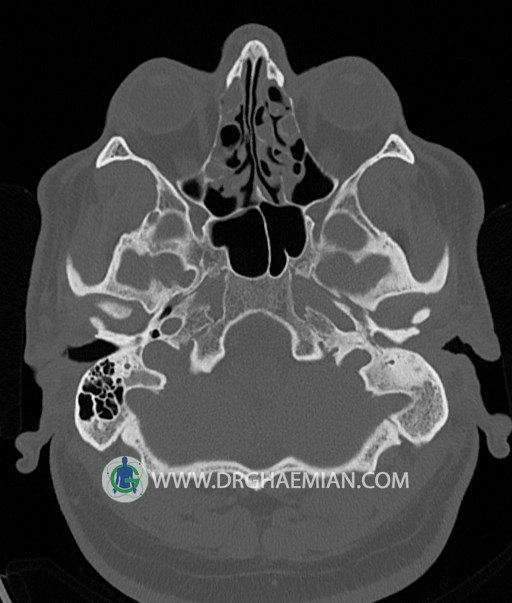

سی تی اسکن گوش داخلی به رادیولوژیست اجازه می دهد تا سطوح مختلف، یا اسلایس هایی از استخوان های که از جمجه به گوش می روند را از طریق امواج ایکس چرخشی مشاهده کند. در این کیس اودیت مدیا، ماستوئیدیت مزمن، اوتیت خارجی، انحراف سپتوم بینی، کونکا بولوزا و افزایش ضخامت سینوس ها مشاهده می شود.

در HRCT از استخوان تمپورال با مقاطع آگزيال ، ساژيتال و کرونال ظريف ( 0.6 mm ) :

– اپاسيتي گوش مياني چپ ناشي از وجود دانسيته نسج نرمي دراطراف استخوانچه ها همراه با اروژن اسکوتوم و

استخوانچه ها بدون جابجايي در رديف استخوانچه ها مشهود است که مطرح کننده اوتيت مديا همراه با نشانه

هاي مشکوک به کولستئاتوم مي باشد .

– اپاسيتي و اسکلروزيس ماستوئيد چپ نشانه ماستوئيديت مزمن

– اپاسيتي کانال گوش خارجي ناشي از دانسيتي نسج نرمي مطرح کننده external otitis